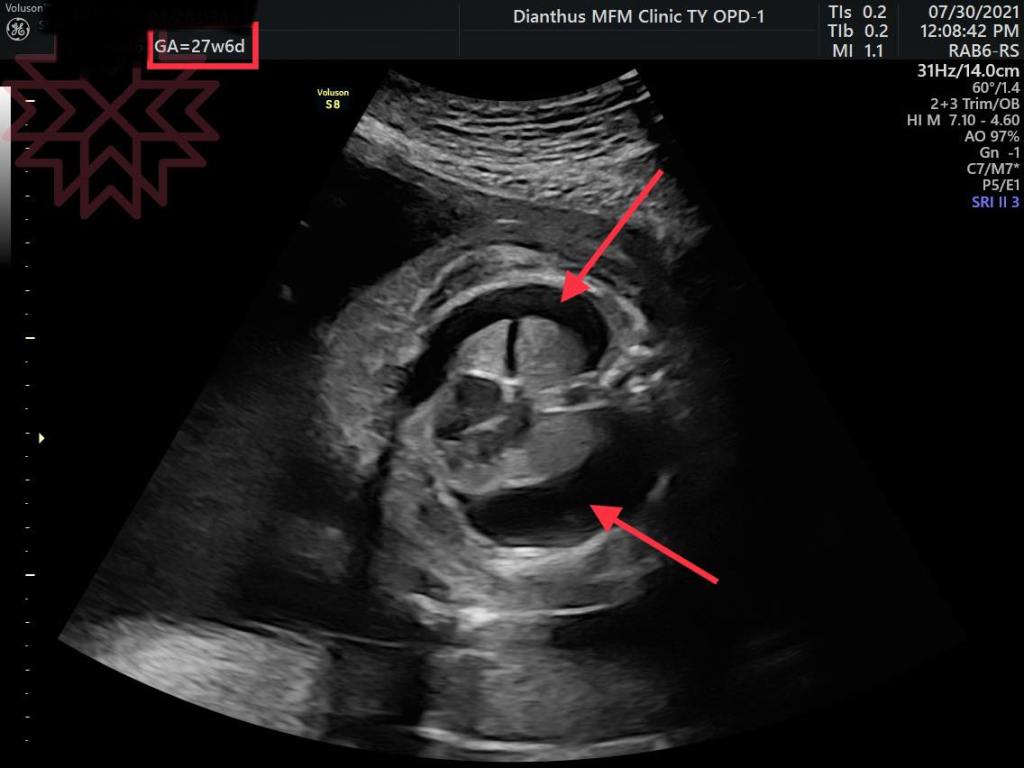

第一張超音波是27周媽咪剛來我門診時候的影像

胎兒雙側乳糜胸